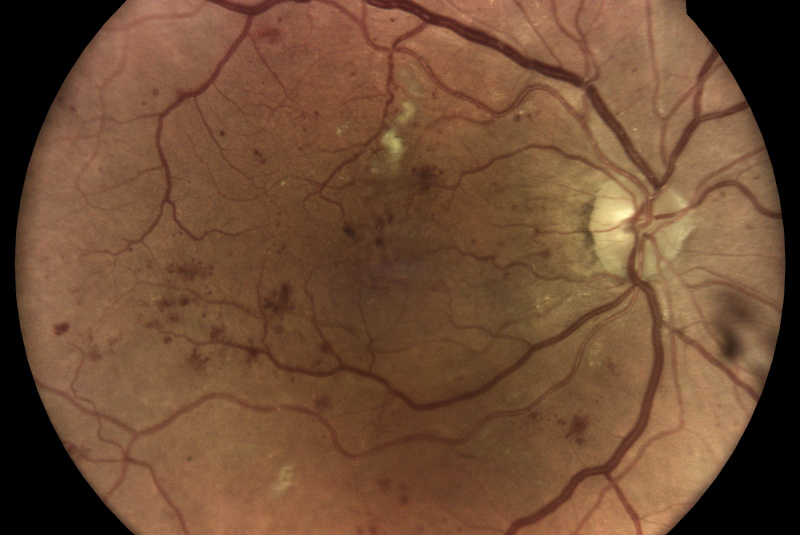

Z vysoko kvalitných fotografií očného pozadia zaobstaraných technológiou iCare DRSplus diagnostikuje diabetickú retinopatiu pomocou umelej inteligencie. Efektívny skríning vyhodnotený softwarom využívajúcim umelú inteligenciu iCare RETCAD®, je schválený pre klinické použitie a je klasifikovaný podľa certifikácie CE (0344) ako zdravotnícky prostiriedok triedy IIa, ktorý šetrí drahocenný čas ako lekára, tak aaj pacienta, umožňuje včasnú intervenciu a pomáha poskytovať včasnú starostlivosť. Analýza pomocou iCare RETCAD® nenahradzuje vyšetrenie zdravotného stavu očí.

AI (umelá inteligencia) okamžite rozpozná práznaky diabetickej retinopatie a klasifikuje výsledky podľa závažnosti na základe medzinárodných klasifikácií. Získate prehľad s hodnotením závažnosti záchytu, kde po analýze snímok zachytených kamerou iCare DRS Plus je automaticky generovaný report o pacientovi so stupnicou závažnosti pre diabetickú retinopatiu na základe medzinárodných štandardov (ICDR, AREDS).

Fundus kamera iCare DRSplus urobí celkovo 4 vysoko kvalitné True Color snímky (dve z pravého a dve z ľavého oka), ktoré sa automaticky ukladajú na cloud a posielajú sa na spracovanie AI - umelej inteligencii. Report je dostupný ihneď a ten je možné prekonzultovať s pacientom počas tej istej návštevy u lekára.